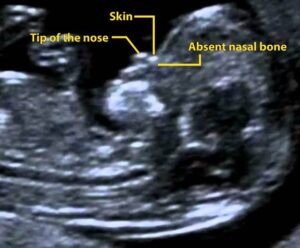

Navigating the world of prenatal care can seem daunting. However, understanding key tests, such as the nasal bone scan in pregnancy, helps ensure the best